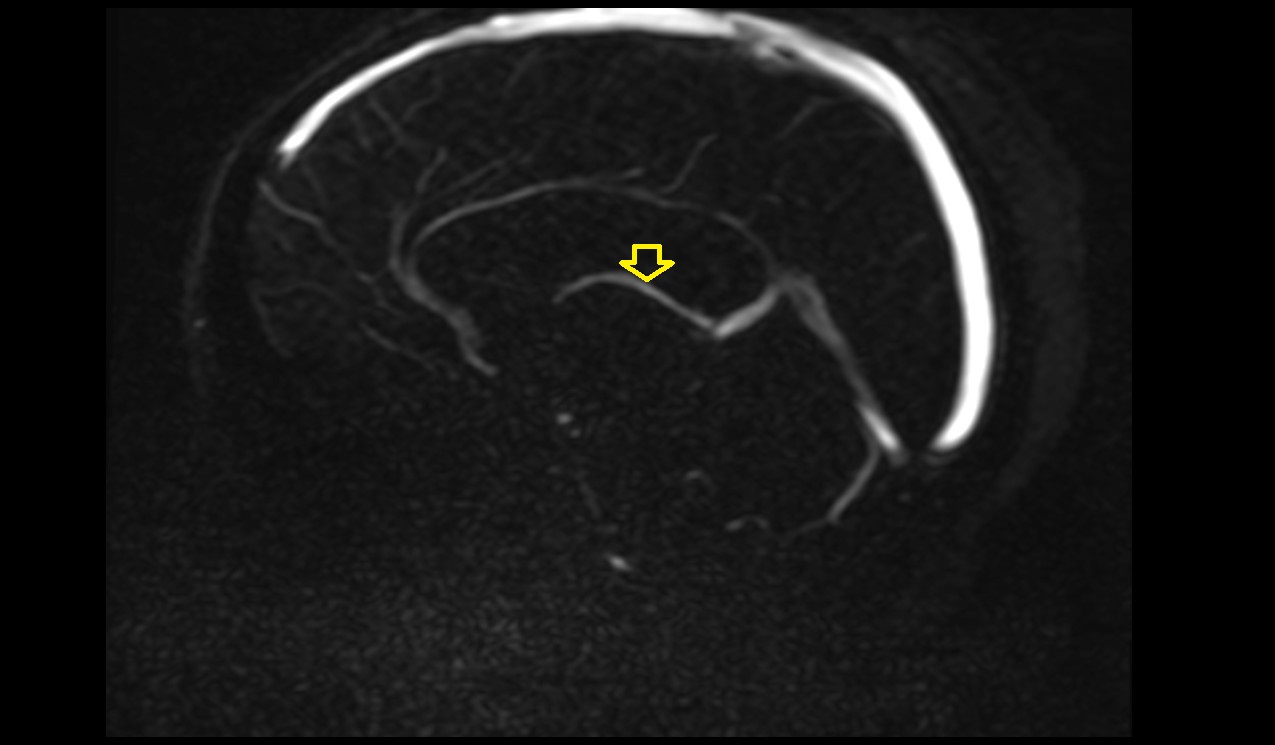

- Superior cortical veins